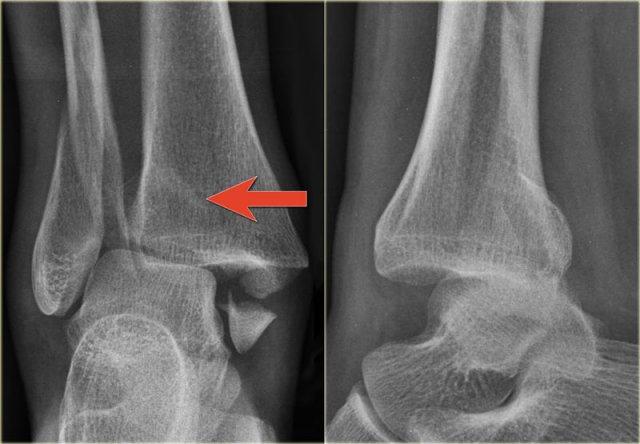

Đây là thêm một số ví dụ về đường tăng tỷ trọng gợi ý gãy tertius.